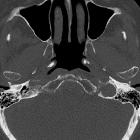

Verkalkungen Tuba auditiva Eustachii

im knorpeligen Anteil der Tuba auditiva eustachii als Zufallsbefund in der Computertomographie bei einer 80-jährigen.

im knorpeligen Anteil der Tuba auditiva als zufälliger Nebenbefund.

Verkalkungen der Tuba auditiva Eustachii sind seltene, meist zufällig entdeckte Nebenbefunde in der Computertomographie, über deren klinische Relevanz spekuliert wird. Diskutiert wird eine mögliche Dysfunktion der Tuba auditiva beim Druckausgleich mit dem Mittelohr bei verminderter Elastizität des Knorpels der Tuba auditive durch die Mineraleinlagerungen.